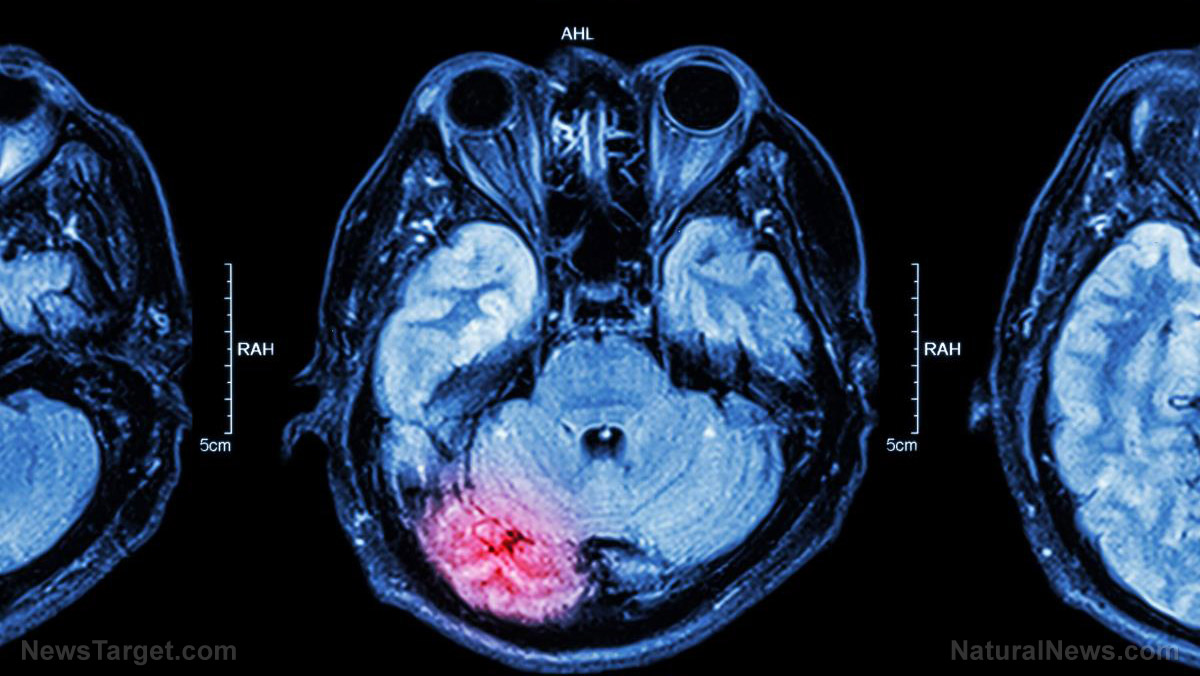

Traumatic brain injury (TBI), aside from causing damage to the brain, can also damage a person’s gut, according to a study published by the University of Maryland School of Medicine (UMSOM). Then, in what can only be a described as a vicious cycle — the damage that he receives in the gut may likely cause more damage to his brain. This disturbing pattern is responsible for the upswing in reported cases of infection and chronic brain damage of patients.

Previous studies have already noted a connection between TBI and gastrointestinal dysfunction, stating that TBI affects intestinal permeability (the ability of the gut to allow materials from the intestine into the bloodstream). However, the study, which was published in the journal Brain, Behavior, and Immunity, was the first to correlate TBI in mice with “delayed, long-term changes in the colon” and link it back to post-traumatic brain inflammation and associated tissue loss.